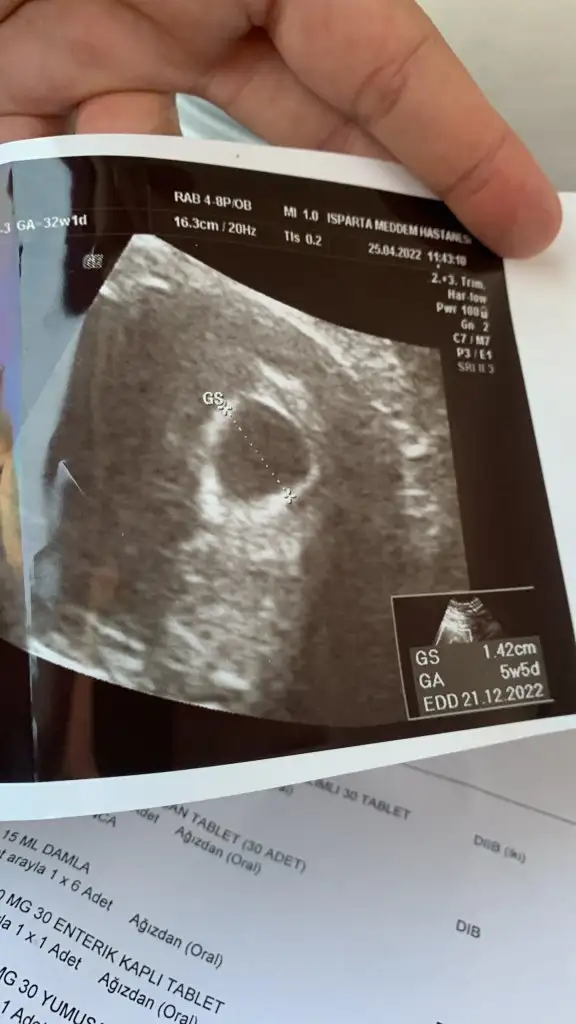

Kız gibi ne oldu cinsiyet belli oldu muEki Görüntüle 2812079 Merhaba tahmin de bulunurmusunuz benim için de karından usg![]()

Tatlim karindansa muayene erkek cinsiyeti çok eminim vajinal muayeneyse kiz çok belli ultrason ..cinsiyeti öğrenince yazar misinYorumlayabilir misiniz ?

Tatlim karindansa muayene erkek cinsiyeti çok eminim vajinal muayeneyse kiz çok belli ultrason ..cinsiyeti öğrenince yazar misin

bu dünkü usg 6+1 im yani :)